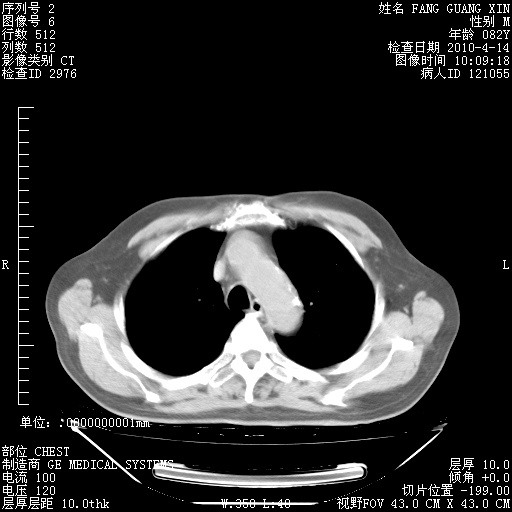

肺部CT平扫未见异常。

4月14日肺部CT